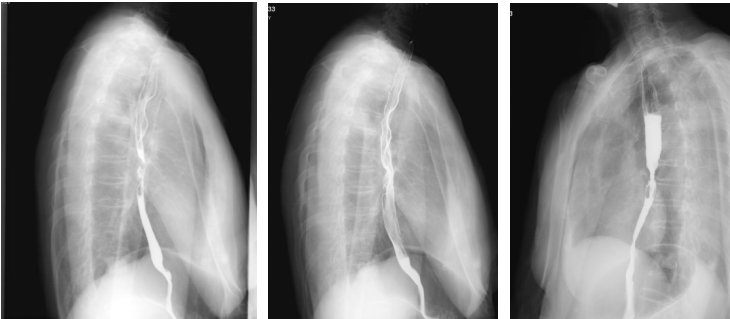

上消化道钡剂造影(2020-08-14):相当于胸7-9椎体水平的食道见范围长约35mm的狭窄段,管壁僵硬,粘膜皱襞破坏、中断,轮廓不光整,可见偏心性充盈缺损及小刺状龛影,狭窄段以上食管轻度扩张,对比剂排空延迟,余食道壁柔软,粘膜规则,未见充盈缺损及龛影,未见异常狭窄及扩张,贲门结构正常,开闭自如。

2020-08-27行放疗CT定位。2020-09-07~2022-10-23行肺部、食管放疗。

GTVp1为食管肿瘤,GTVp2为肺肿瘤。

分割方式:

95%PGTVp1:60Gy/2Gy/30F;

95%PGTVp2:60Gy/2Gy/30F;

后肺原发灶补量照射:95%PGTVp2:8Gy/2Gy/4F。